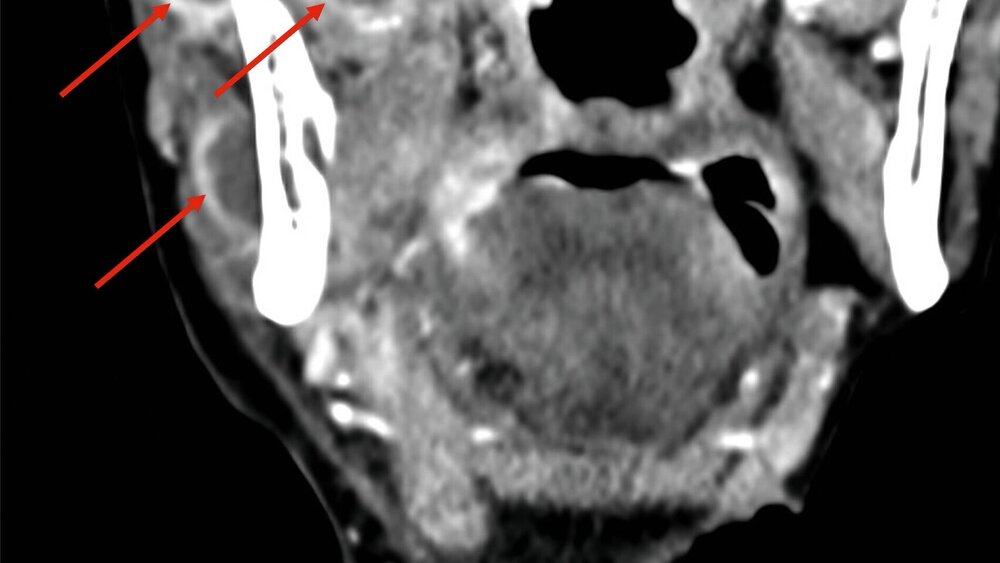

Eine im Verlauf angefertigte CT-Diagnostik zeigte trotz der initialen chirurgischen Eingriffe multiple Abszessformationen medial und lateral angrenzend an den Ramus mandibulae rechts sowie kaudal an die Lamina lateralis des Processus pterygoideus des Os sphenoidale (Abbildung 1).